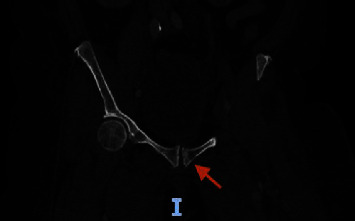

背景:目前,用于探讨癌症患者静脉血栓栓塞症构成的数据极少。本病例报告讨论了一名高级别尿路上皮癌患者的静脉血栓栓塞症状,并重点介绍了血栓的病理学发现。病例介绍。一名 55 岁的女性患者被诊断为高级别尿路上皮癌并有多处转移,左下肢出现广泛的深静脉血栓。由于左下肢疼痛和肿胀,抗凝治疗无效,因此需要进行血管内再通术。医生为她进行了机械性血栓切除术,并将样本送去进行病理检查。病理检查发现了微小的转移癌碎片,并混有层状血块(血栓)。转移癌的形态和免疫染色谱与膀胱转移癌相符:据估计,约有 4-20% 的癌症患者会在某个阶段出现 VTE,确诊后初期的 VTE 发生率最高。每年有 0.5% 的癌症患者会出现血栓,而普通人群的发病率为 0.1%(Elyamany 等人,2014 年)。尽管知道癌症患者的 VTE 发生率增加,但迄今为止分析癌症患者血栓组成的研究却很少。

Background: Currently, minimal data are available to explore the composition of venous thromboembolism in patients with cancer. This case report discusses a presentation of venous thromboembolism in a patient with high-grade urothelial carcinoma and highlights the pathology findings in thrombi. Case Presentation. A 55-year-old female who was diagnosed with high-grade urothelial carcinoma with multiple metastases developed an extensive deep vein thrombosis in her left lower extremity. Endovascular revascularization was indicated due to left lower extremity pain and swelling not responsive to anticoagulation. A mechanical thrombectomy was performed, and samples were sent for pathology. Pathologic examination discovered minute fragments of metastatic carcinoma, admixed with laminated blood clots (thrombus). The morphology of metastatic carcinoma and the immunostain profile were compatible with metastatic carcinoma of bladder origin.